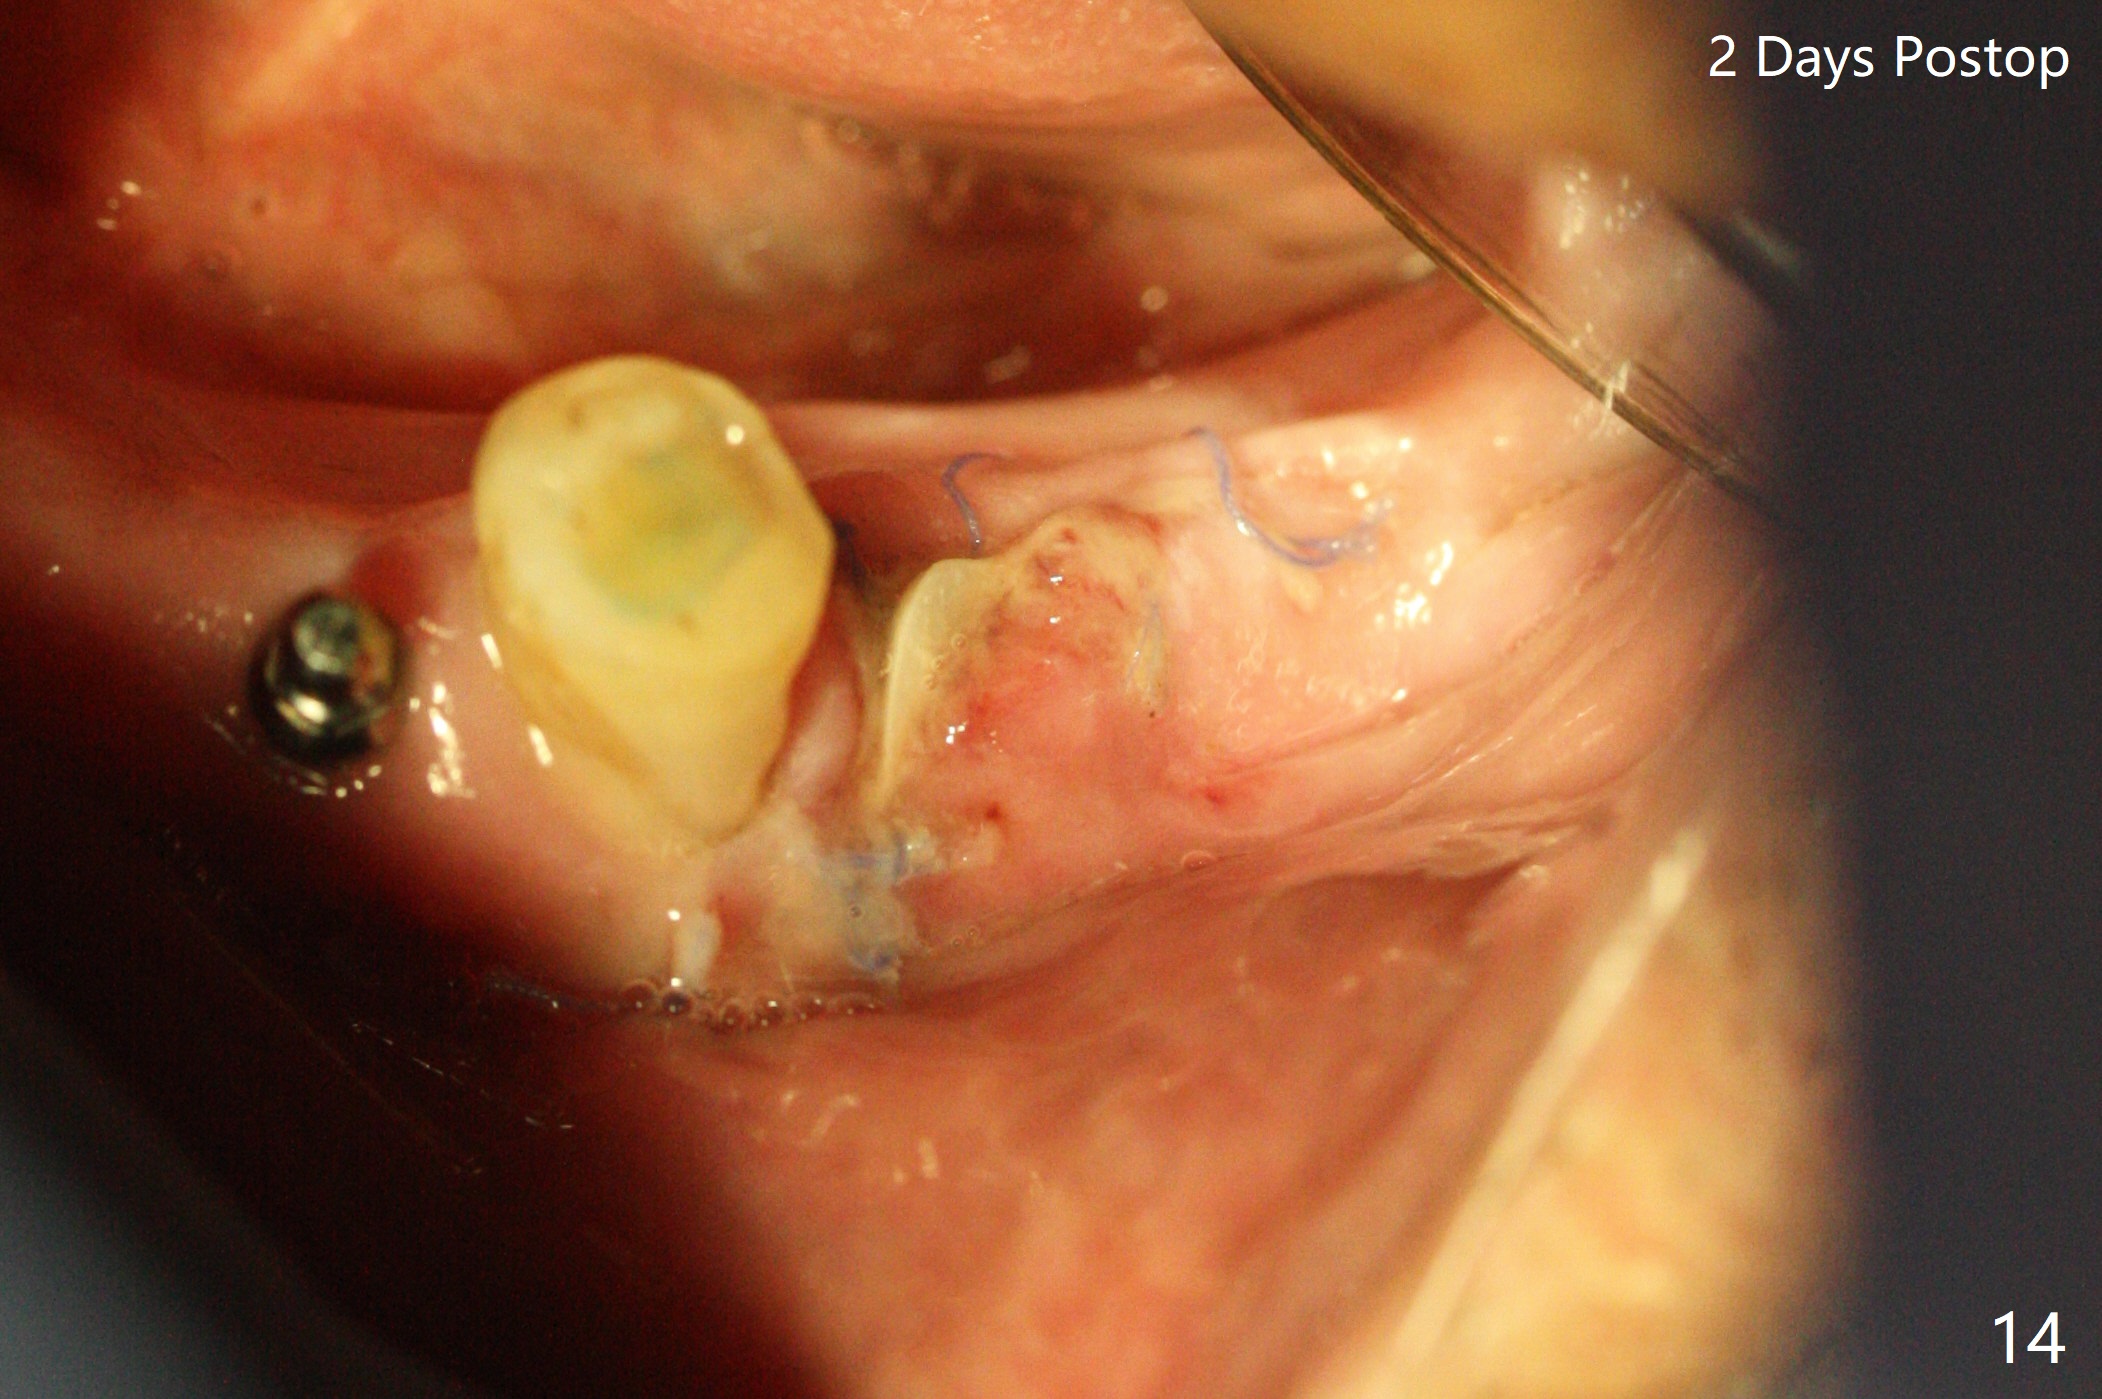

The patient has to wear the RPD for mastication.  It would be more painful without it.  Later the tissue surface of the RPD is trimmed.